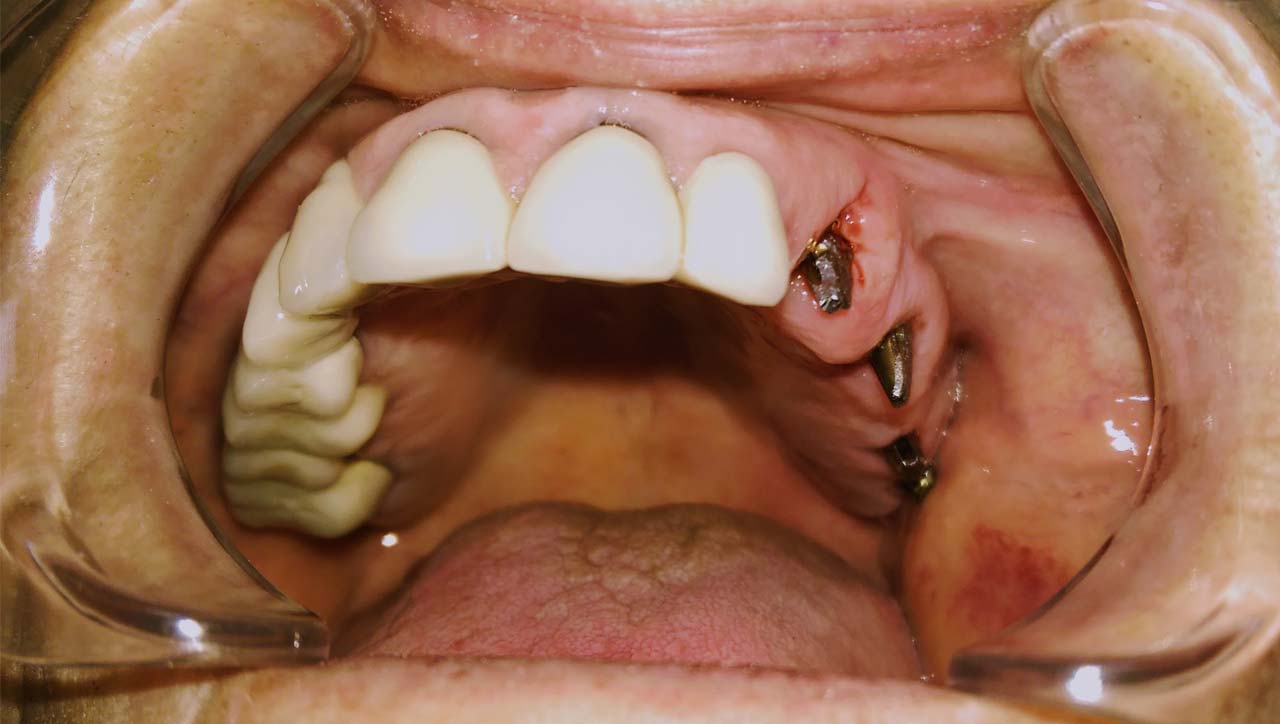

A hiányzó fogak pótlására modern kezelési eljárások állnak rendelkezésre. A páciensek sokszor szeretnék, ha az új fogak minél hamarabb a helyükre kerülnének. A hagyományos módszerek szerint, a fogorvosok a beültetés után 4-6 hónapot várnak, mielőtt megfelelő fogpótlást rögzítenének rá.

Fokozatosan terjed az azonnal terhelhető implantátum tendenciája. Mindkét lehetőségnek vannak előnyei és korlátai. Ezért a fogorvosoknak mérlegelniük kell, mielőtt a kezelés helyes útjáról döntenek.

A hagyományos implantátum terhelés során az implantátumot a behelyezést követő 4-6 hónapos gyógyulási időszakot követően terhelik. Az azonnal terhelhető implantátum az idegen szövet behelyezését követő 48 órán belül történő terhelését igényel.

A hagyományos terheléssel ellentétben, az azonnal terhelhető implantátum jelentősen csökkenti az implantátum behelyezése és a terhelés közötti várakozási időt, valamint a fogorvosnál tett látogatások számát. Az ilyen implantátummal elkerülhető a fogak hosszú távú hiánya által okozott elváltozások az arcon.